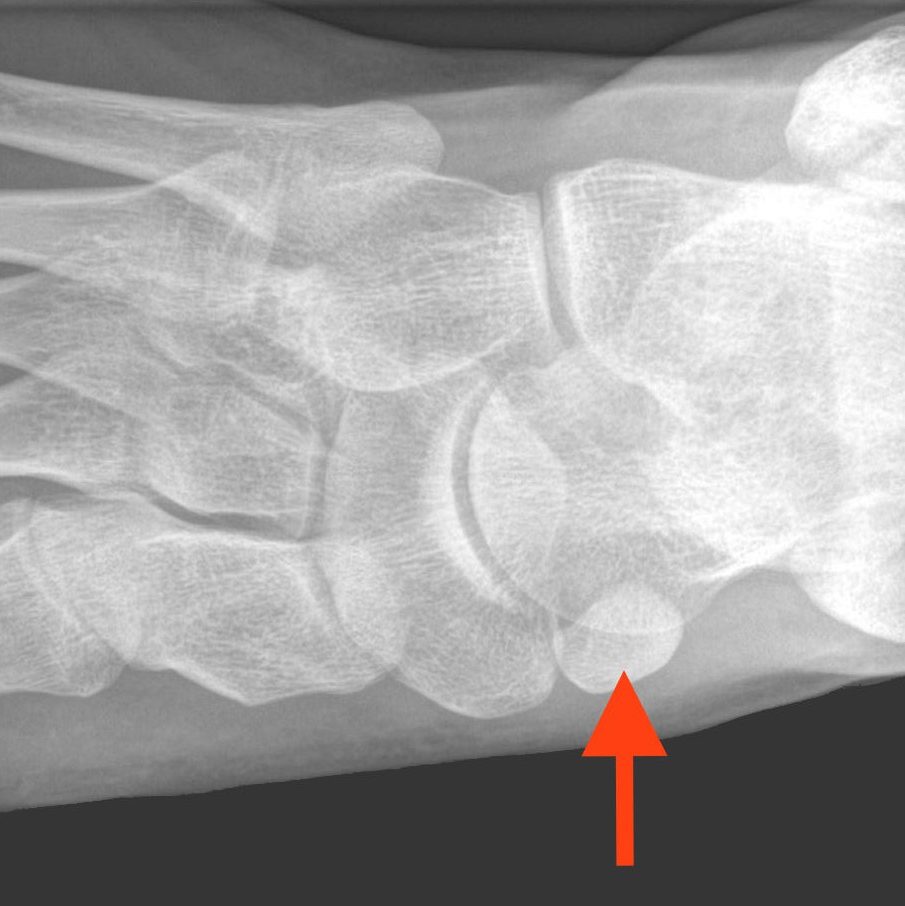

Bunions, hammertoes, and flat feet oh my! I discuss common bone and structural deformities of the foot and ankle, including arthritis…and how they can be treated. Click on the buttons below each image for more information.